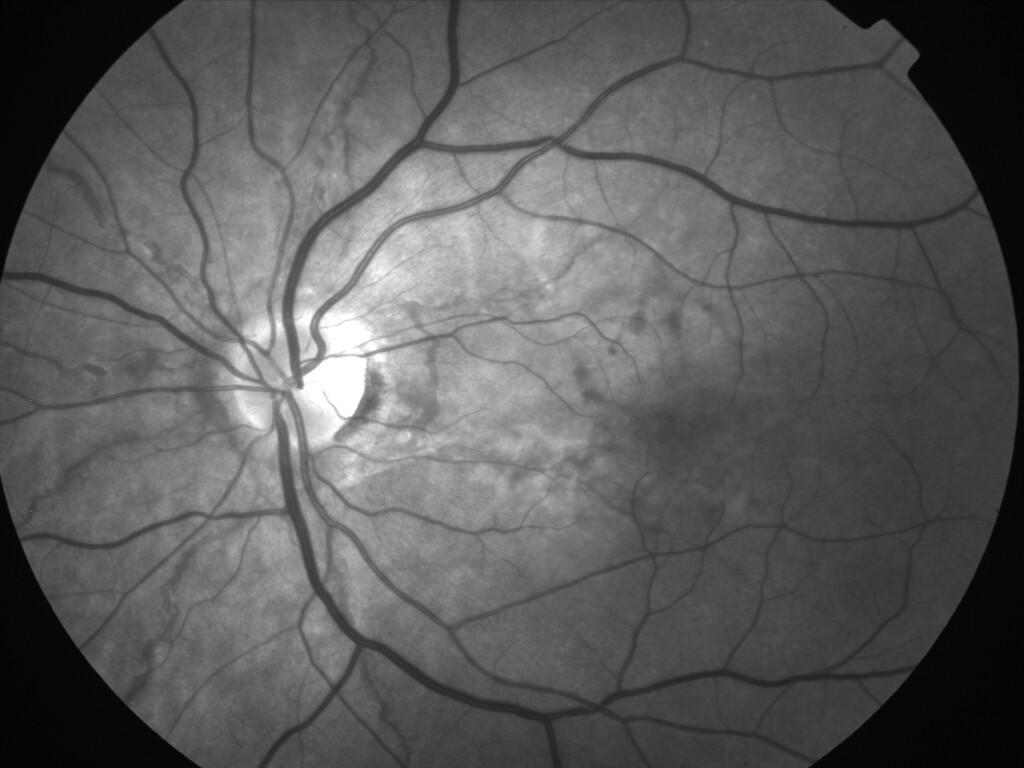

ASSOCIATION STRIES ANGIOIDES ET DYSROPHIE MACULAIRE RETICULEE

NEOVASCULARISATION